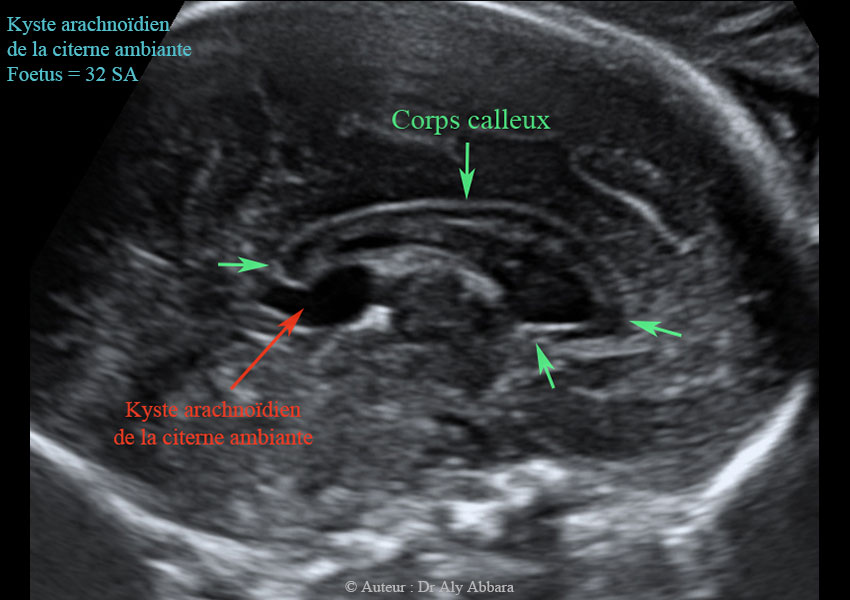

Agenesie Du Corps Calleux

Mon corps après bébé-Quand il existe chez un enfant, ou un adulte, des signes cliniques qui peuvent évoquer une anomalie du corps calleux quand un accident (traumatisme) ou une pathologie sans rapportSon absence, appelée l'agénésie du corps calleux, est une malformation cérébrale congénitale Rien ne remplace cette structure d'une dizaine de centimètres, hormis du liquide

Accueil du Forum Maladies neurologiques et musculaires Agénésie du corps calleux Le Forum maladies rares est un espace de partage d'informations et d'expériences pour lesLe corps calleux se développe in utero entre la dixième et la vingtième semaine de gestation L'agénésie du corps calleux est une malformation cérébrale congénitale dans laquelleEn agénésie primaire le

Parcourez 304 photos et images disponibles de corps calleux, ou lancez une nouvelle recherche pour explorer plus de photos et images cerveau xray (large) corps calleux photos et imagesLe diagnostic de ces deux affections est fait àL'agénésie du corps calleux désigne une malformation du cerveau consécutive à